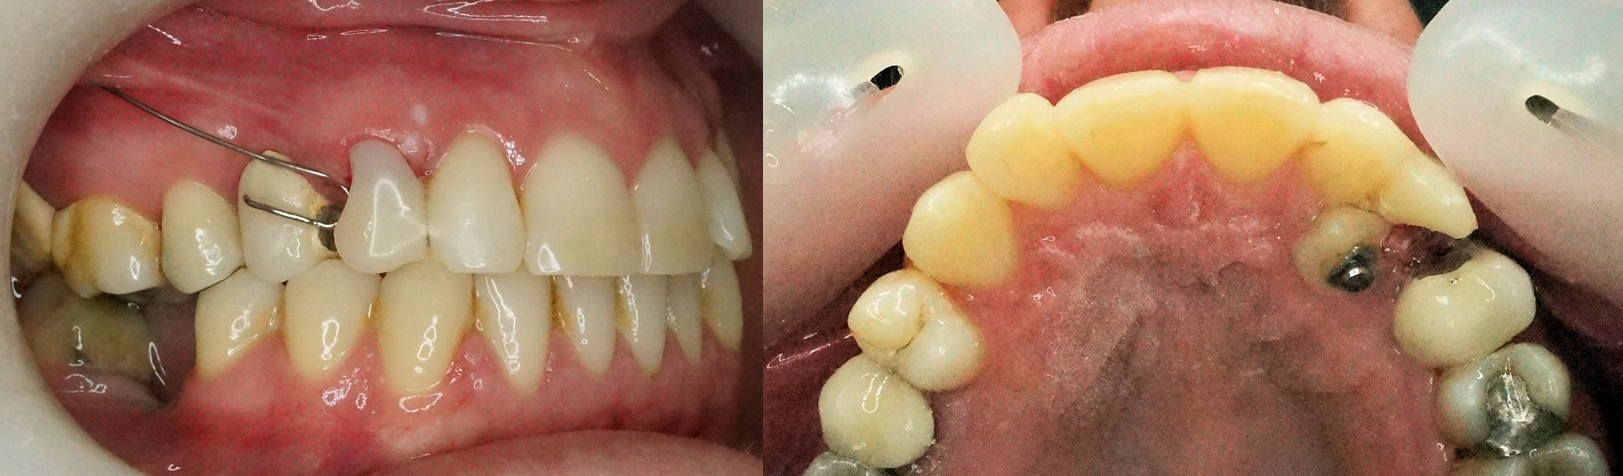

Une fois la couronne apparue, le bras du CT8 peut lui-même effectuer certaines finitions si nécessaire : complément d’égression, distalisation, correction des rotations. La seule limite est le torque.

Résultats

La canine fait éruption à son emplacement naturel. Le CT8 peut agir d’une manière totalement autonome, sans autre appareil si l'occlusion est acceptable par ailleurs.

Le CT8 peut être utilisé de façon esthétique en gardant la canine temporaire ou en complément d’une facette résine collée.